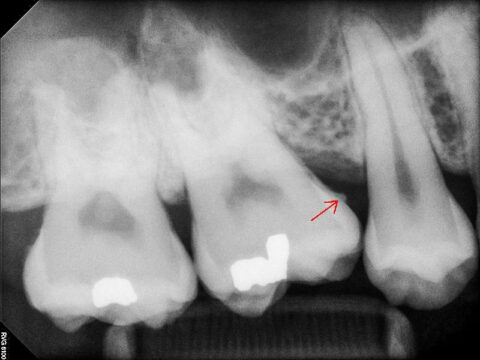

Sarro observado en los dientes radiográficos de la gente moderna. El área pequeña indicada por la flecha del medio a la derecha es el cálculo y el color blanco indica el tratamiento de caries. © WikiCommons / ANUG